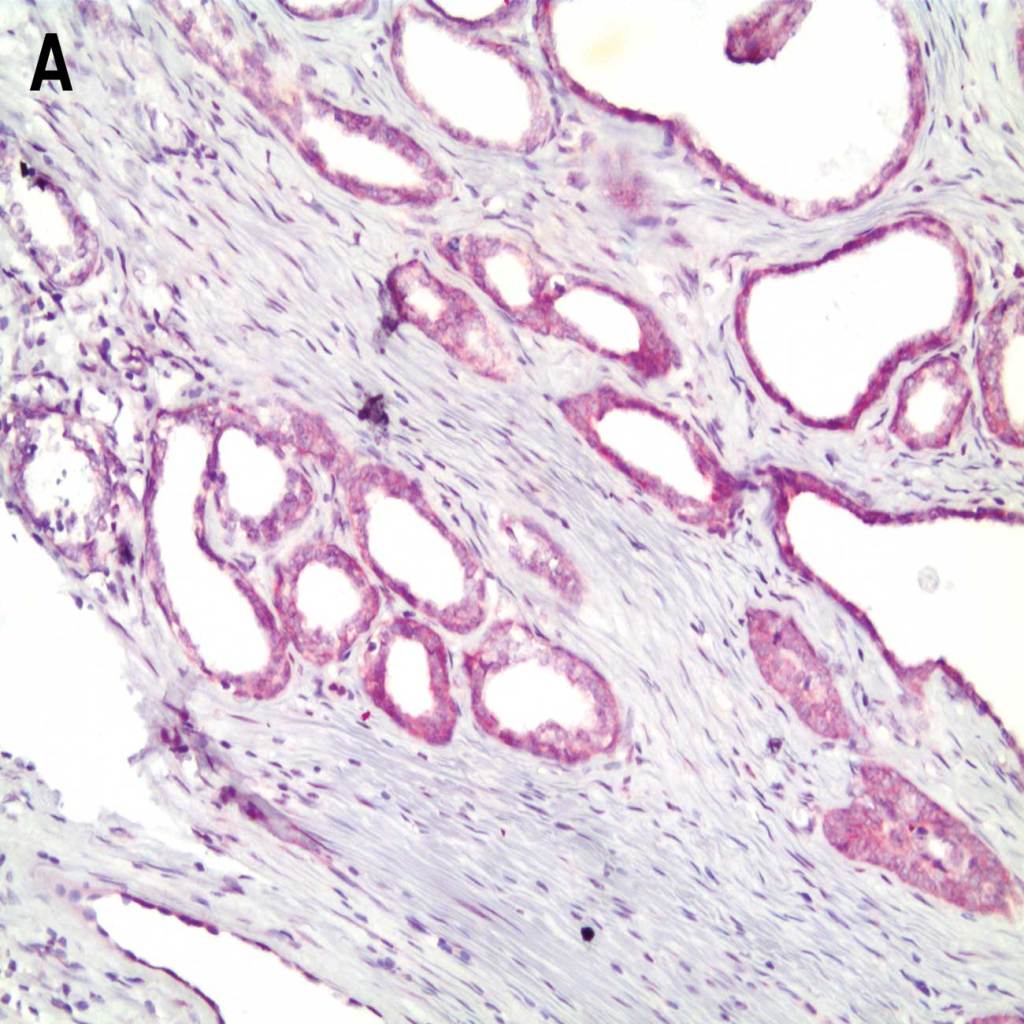

HER-2 detected in breast cancer tissue with A.-B. AMPIVIEW® HER-2 (AS) Dig RNA Probes and C.-D. with AMPIVIEW® NSP Dig RNA Probes (negative control probe). AMPIVIEW® RNA probes have been amplified with DIGX® rabbit anti-digoxigenin linker and detected with POLYVIEW® PLUS AP (anti-rabbit) reagent, combined with HIGHDEF® Red AP Chromogen Kit and counterstained with HIGHDEF® Hematoxylin.